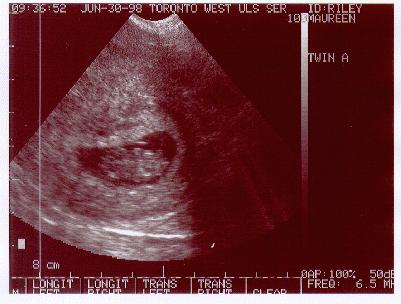

June 30, 1998

8 Weeks, 5 Days

Twin "A"

This is our first "good" ultrasound of "Abigail" (Twin "A").

Please don't ask me to point out anything! When I saw the image

on the screen as the technician was doing the measurements, I figured the

head was on the right and body on the left, but of course the head is on

the left and the body on the right! I guess I won't be changing my profession.

BUT the important thing about this ultrasound, is that it was the

first time we saw a Heartbeat.

The Doctor says the baby is a good size for its stage of development.

(FYI: The twin closest to the cervix is termed "Twin A") |